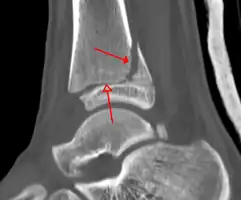

X-ray

On X-rays, there can be a fracture of the medial malleolus, the lateral malleolus, or of the anterior/posterior margin of the distal tibia. [17] If both the lateral and medial malleoli are broken, this is called a bimalleolar fracture[18]. If the posterior malleolus is also fractured, this is called a trimalleolar fracture. [19]

A triplane fracture of the ankle as seen on CT